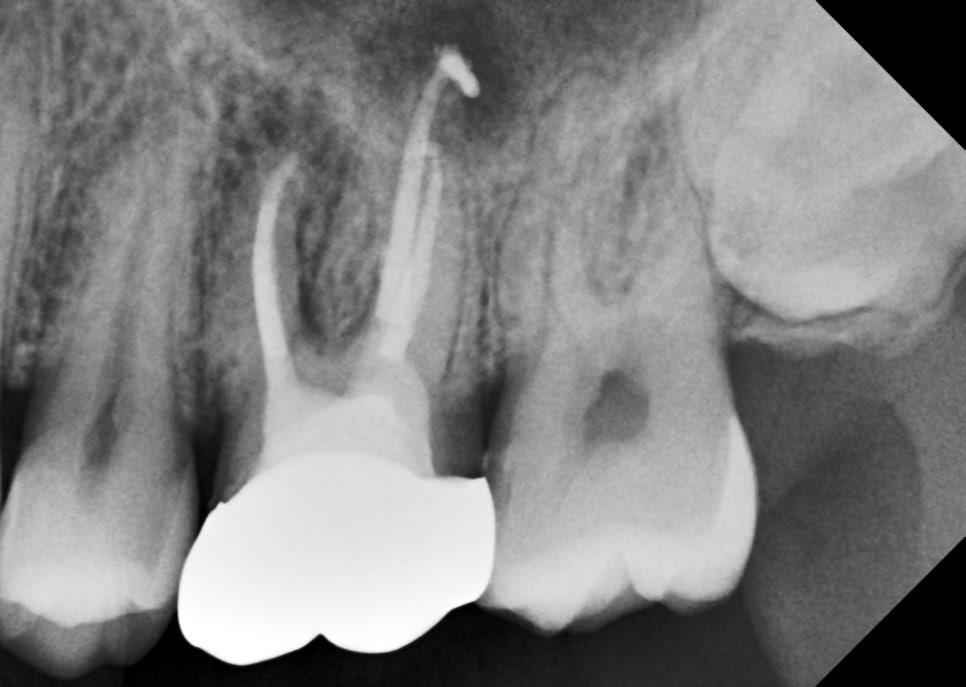

크라운 시적 엑스레이

통증도 완전히 사라지셨고

염증도 서서히 잡혀가고 있어서

만들어온 크라운을 시적해보고

엑스레이를 다시 찍었습니다.

치아 뿌리와 크라운 경계가

턱이 지지 않고

스무스하게 잘 연결됐는지

평가하는 거예요.

턱지지 않고 잘 만들어져서

바로 붙여드렸습니다.